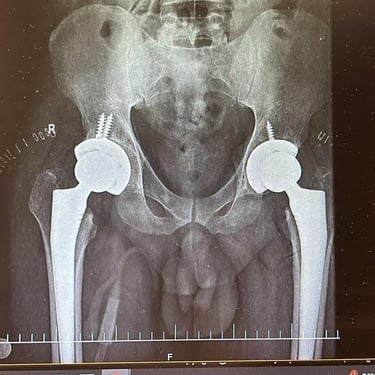

Hip replacement surgery and revision surgery

Gallery